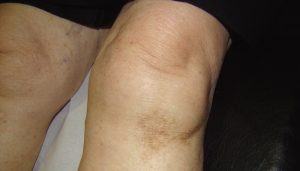

Une dermatose chez une patiente de 79 ans

Mme P., 79 ans, consulte, car elle souffre de ses 2 genoux. Lors de l’examen de ces derniers, nous sommes frappés par la présence d’un placard de couleur brune sous…